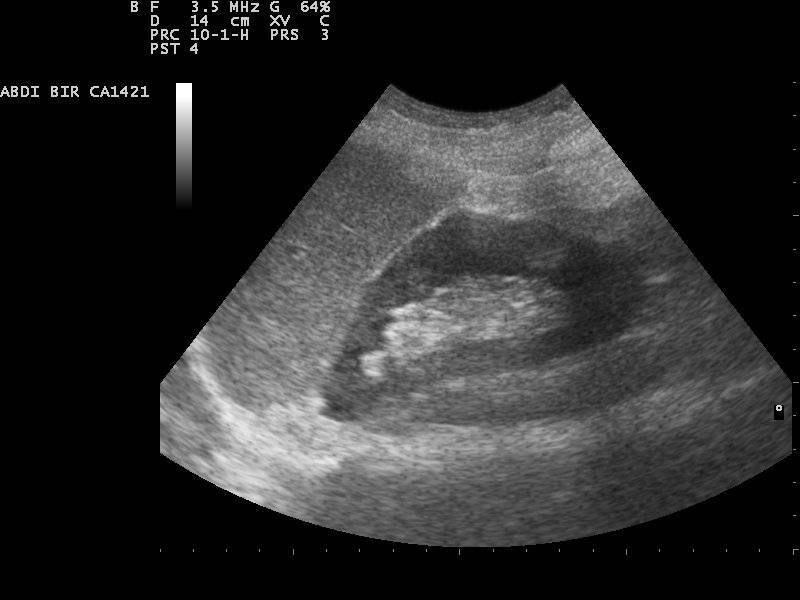

به هر حال، برای تشخیص کیست کلیه، باید از سونوگرافی، تصویربرداری مغناطیسی (MRI) و یا تصویربرداری کامپیوتری (CT) استفاده کرد.